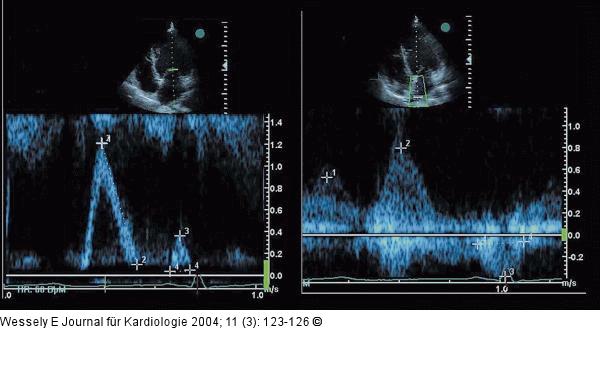

Abbildung 6: Aortenklappeninsuffizienz - Endokarditis Gleichzeitige Darstellung des Einstroms über die Mitralklappe (oben) und die obere rechte Pulmonalvene (unten) in der PW-Dopplerregistrierung; vorzeitig endende A-Welle transmitral bezogen auf die linksatriale Kontraktion |

Abbildung 6: Aortenklappeninsuffizienz - Endokarditis

Gleichzeitige Darstellung des Einstroms über die Mitralklappe (oben) und die obere rechte Pulmonalvene (unten) in der PW-Dopplerregistrierung; vorzeitig endende A-Welle transmitral bezogen auf die linksatriale Kontraktion |